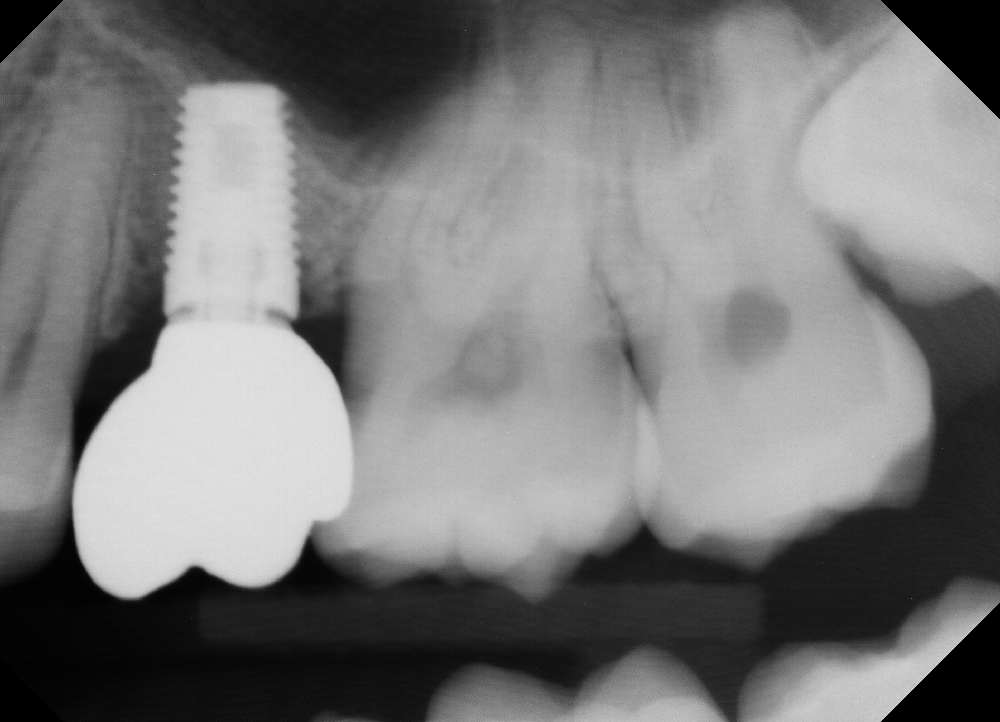

Anthony A.

This patient had only a few remaining infected teeth, but didn’t want to settle for just a denture.  Placed multiple implants and provided a secure fixed option which allowed him to not only chew better but to smile again.